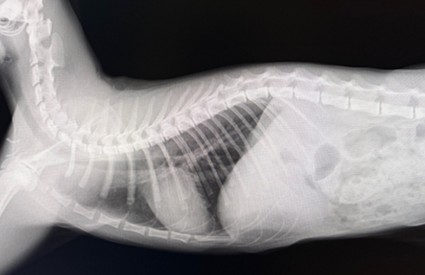

その後は開腹部も縫合し、終了です。                                           翌日に確認のレントゲンを撮り再発がないか確認したのが下の写真です。綺麗に胃が腹腔内に収まっているのが分かります。

術後1日目